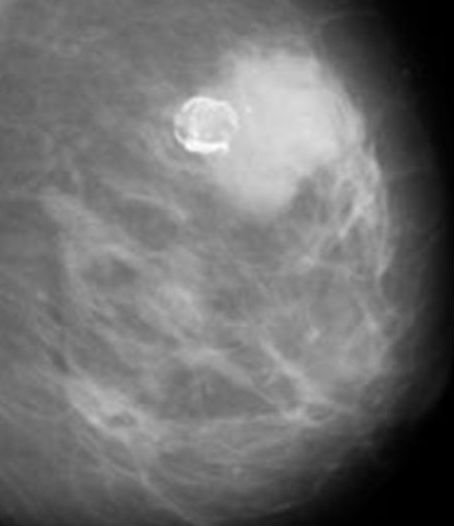

- Маммография использует рентгеновские лучи для получения изображения ткани молочной железы.

Это изображение называется маммограммой. Он определяет границы фиброаденомы и отличает ее от других тканей. Но маммография может быть не лучшим тестом для визуализации фиброаденом у молодых людей, у которых может быть плотная ткань груди. Из-за плотной ткани трудно увидеть разницу между типичной тканью молочной железы и тем, что может быть фиброаденомой. Кроме того, из-за риска облучения при маммографии они, как правило, не используются для проверки уплотнений молочной железы у людей моложе 30 лет.